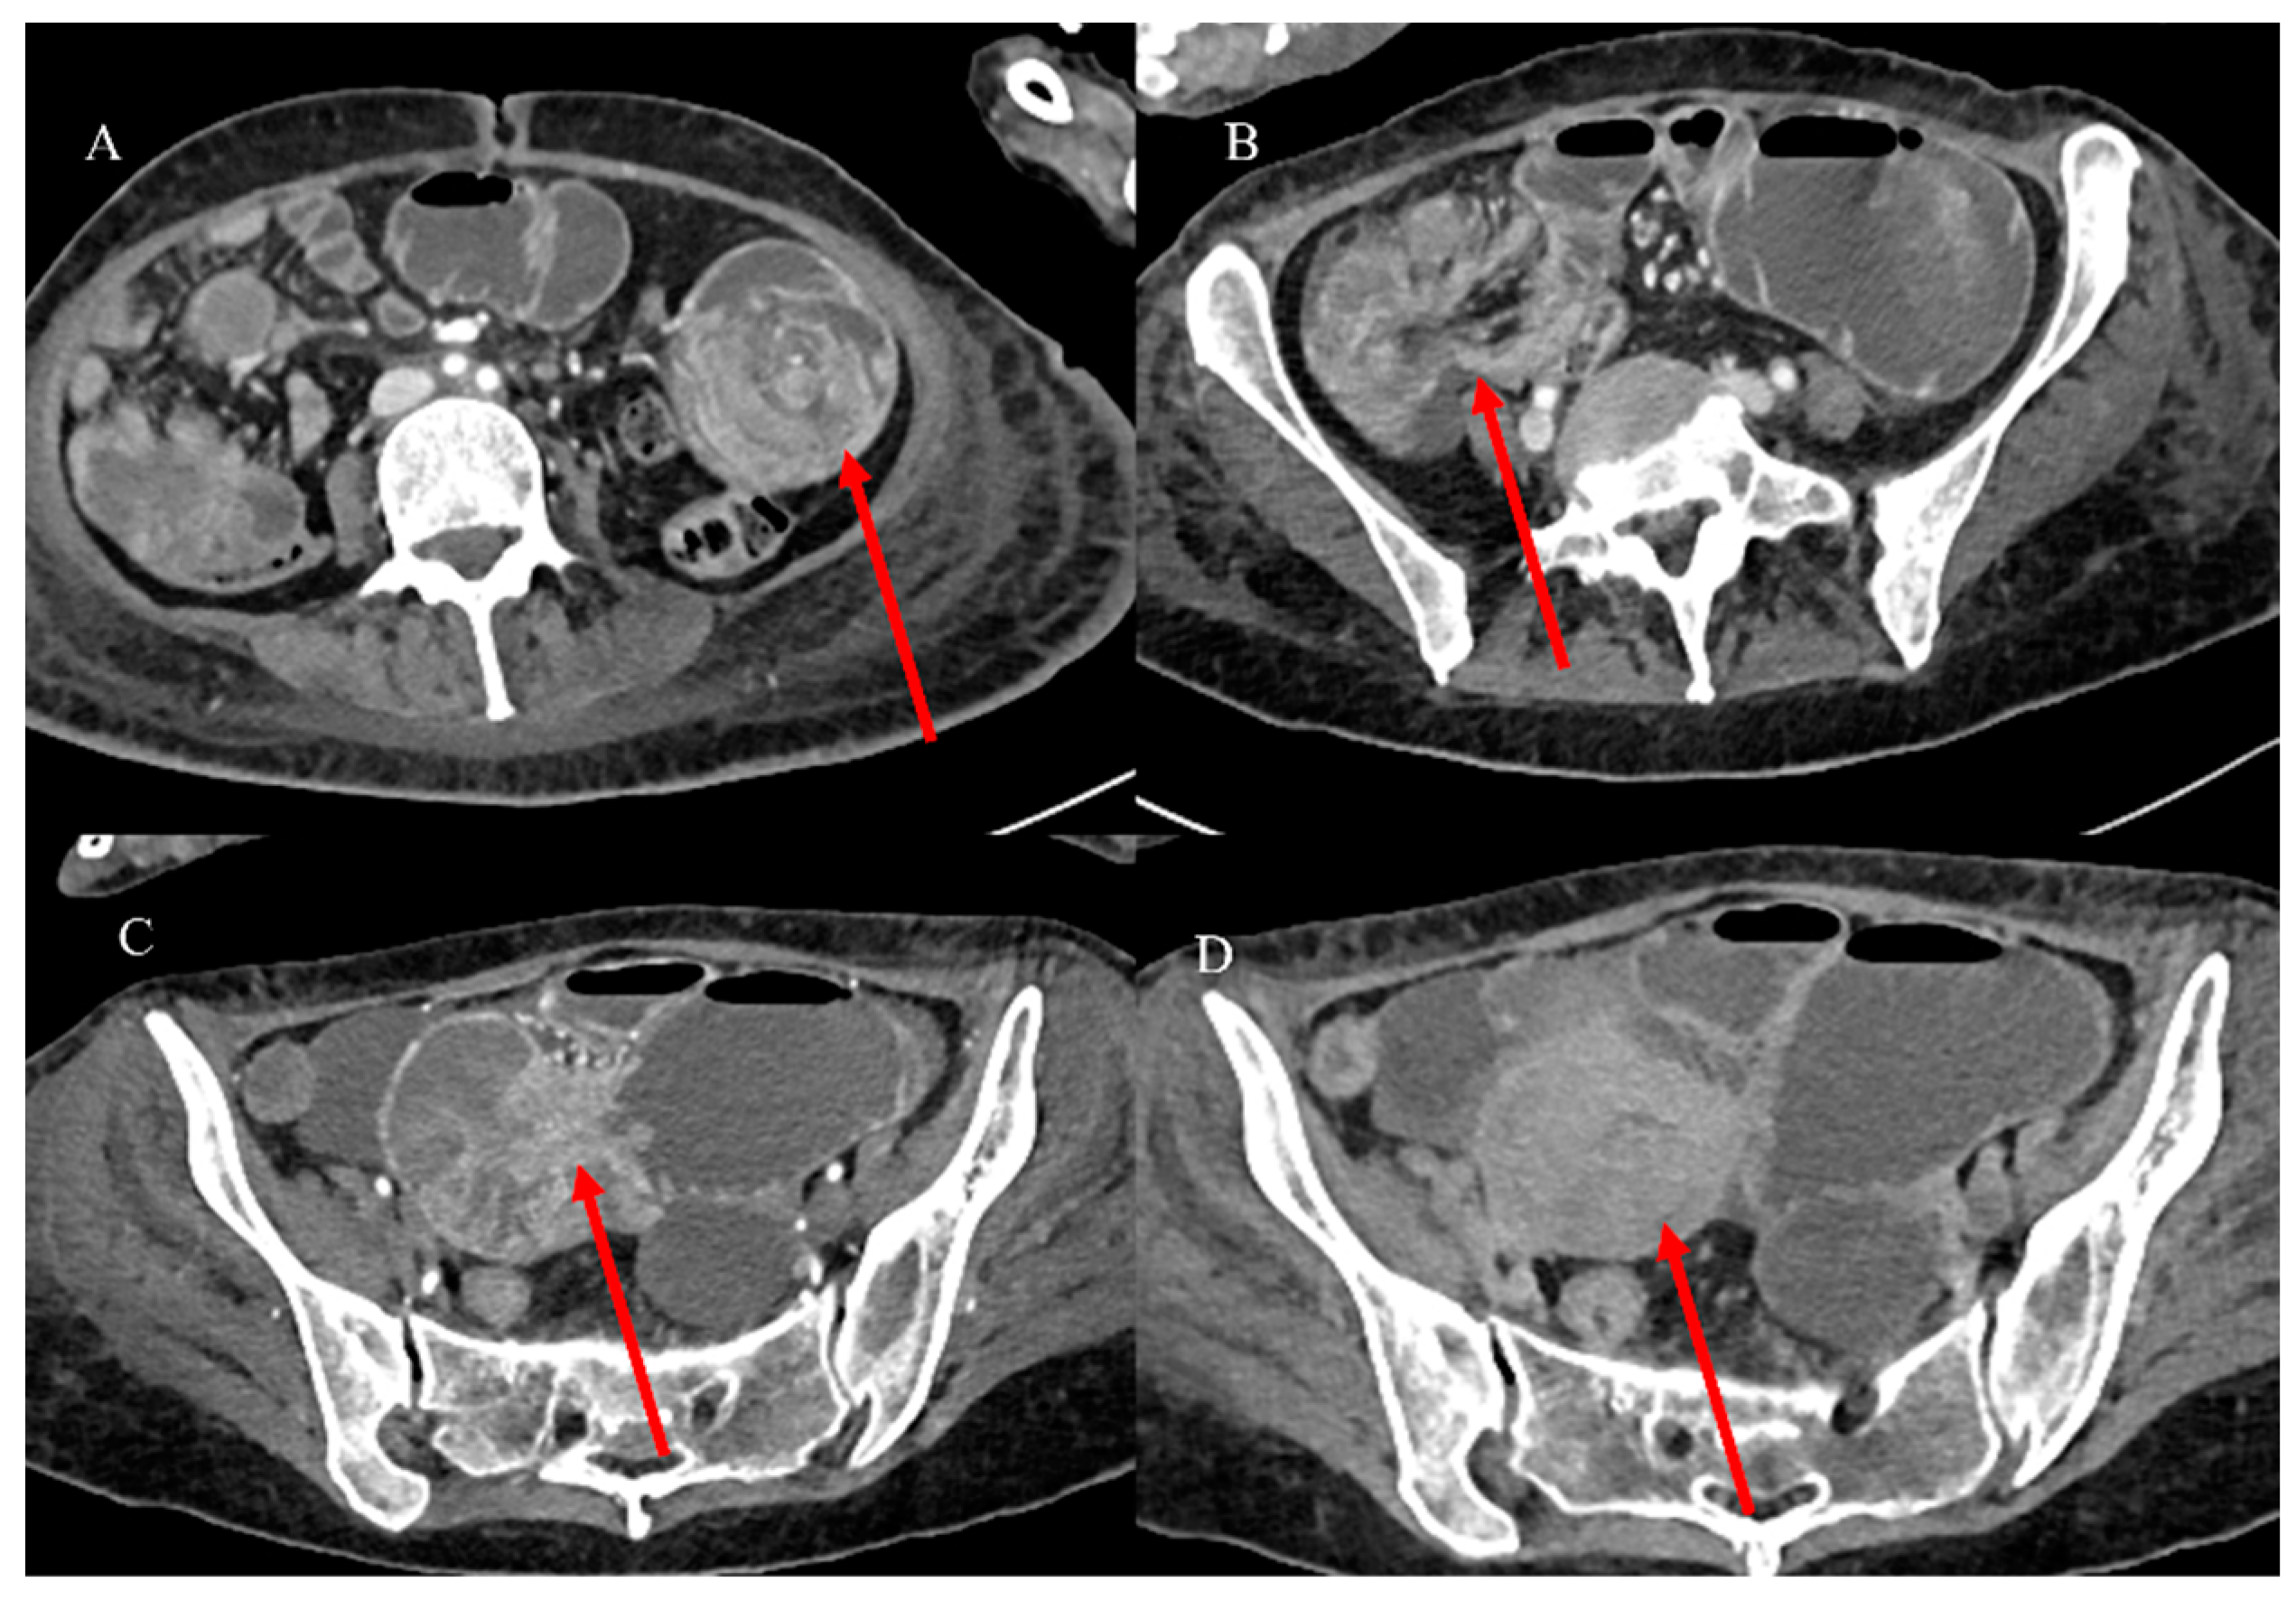

- Marsicovetere, P.; Ivatury, S.J.; White, B.; Holubar, S.D. Intestinal intussusception: Etiology, diagnosis, and treatment. Clin. Colon. Rectal Surg. 2017, 30, 30–39. [Google Scholar] [CrossRef] [PubMed]

- Kim, Y.H.; Blake, M.A.; Harisinghani, M.G.; Archer-Arroyo, K.; Hahn, P.F.; Pitman, M.B.; Mueller, P.R. Adult intestinal intussusception: CT appearances and identification of a causative lead point. Radiographics 2006, 26, 733–744. [Google Scholar] [CrossRef]

- Choi, S.H.; Han, J.K.; Kim, S.H.; Lee, J.M.; Lee, K.H. Intussusception in adults: From stomach to rectum. AJR Am. J. Roentgenol. 2004, 183, 691–698. [Google Scholar] [CrossRef]

- Panzera, F.; Di Venere, B.; Rizzi, M.; Biscaglia, A.; Praticò, C.A.; Nasti, G.; Mardighian, A.; Nunes, T.F.; Inchingolo, R. Bowel intussusception in adult: Prevalence, diagnostic tools and therapy. World J. Methodol. 2021, 11, 81. [Google Scholar] [CrossRef] [PubMed]

- Honjo, H.; Mike, M.; Kusanagi, H.; Kano, N. Adult intussusception: A retrospective review. World J. Surg. 2015, 39, 134–138. [Google Scholar] [CrossRef] [PubMed]

- Wang, N.; Cui, X.Y.; Liu, Y.; Long, J.; Xu, Y.H.; Guo, R.X.; Guo, K.J. Adult intussusception: A retrospective review of 41 cases. World J. Gastroenterol. World J. Gastroenterol. 2009, 15, 3303. [Google Scholar] [CrossRef]